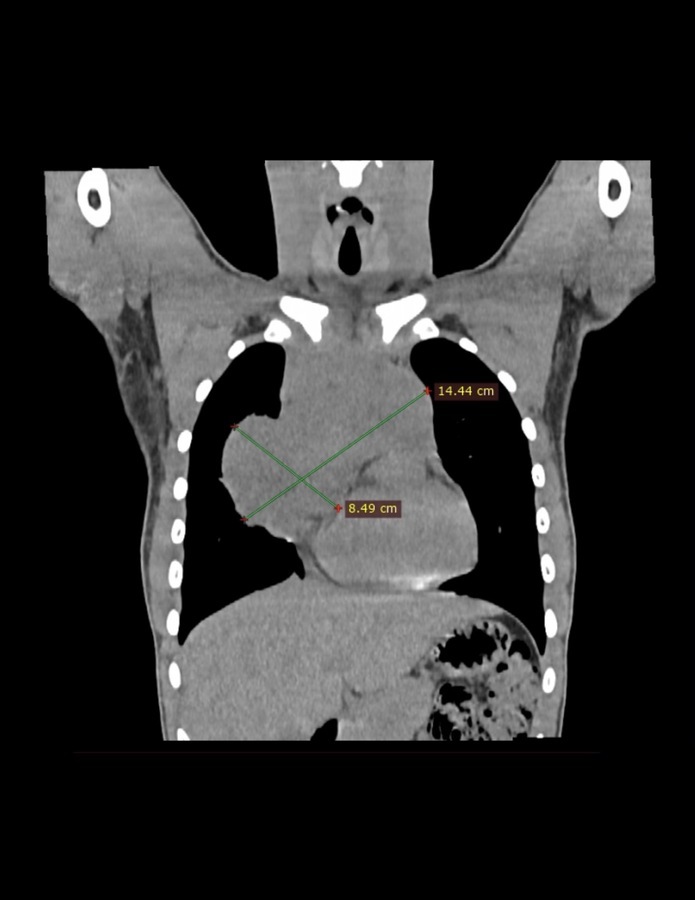

Пухлини середостіння у дітей є одними з найпідступніших патологій. Розташовуючись поруч із серцем, великими судинами та дихальними шляхами, вони часто спричиняють задишку, постійний кашель та інші серйозні симптоми. Значна частина таких пухлин має злоякісний характер, що потребує негайного та комплексного втручання.

Ці два випадки були особливо складними через великий об’єм новоутворень. Хірургічне втручання вимагало не лише ювелірної точності від операційної бригади, а й детального планування кожного кроку — від першого розрізу до анестезіологічного супроводу.